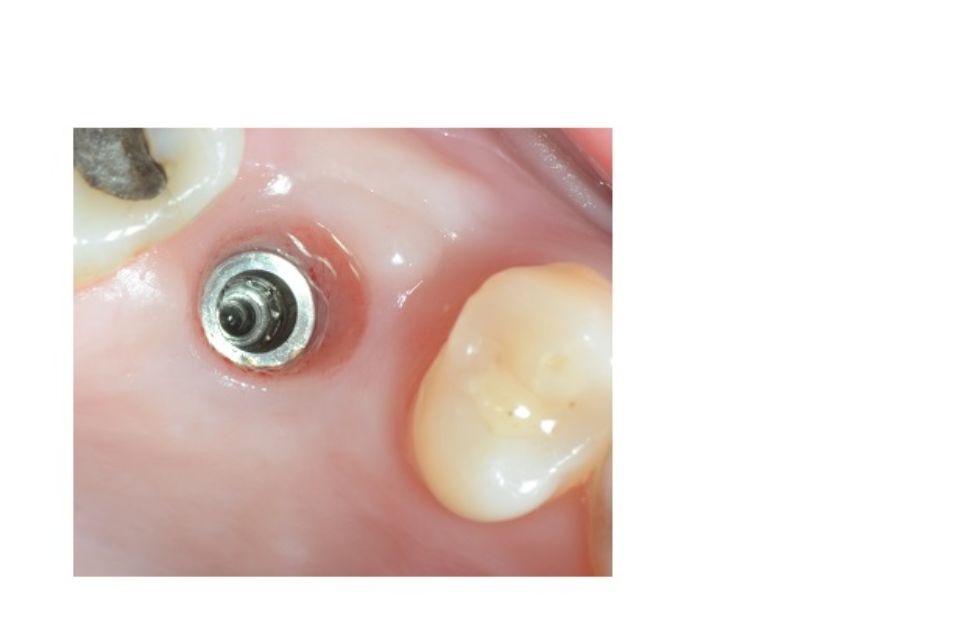

Implantologia bucal

La implantologia és l´especialitat odontològica que s´ocupa de la substitució de l´arrel de la dent perduda.

La substitució es fa mitjançant una petita intervenció quirúrgica per col·locar una peça de titani dins de l'os maxil·lar.

L'implant té una rosca al seu interior on posteriorment s'enroscarà el pilar que suportarà la corona protètica.

Després de la valoració de l'implantòleg i un diagnòstic molt acurat per part de l'equip professional, es plantegen diferents solucions. Depenent del problema plantejat que pot ser: pèrdua unitària, pèrdua múltiple o desdentat complet...es realitzarà la tècnica precisa per tal de millorar la qualitat de vida del pacient.

La implantologia és una de les àrees mèdiques que més ha evolucionat en els darrers anys. Això fa que la fiabilitat i la comoditat del pacient augmenti.